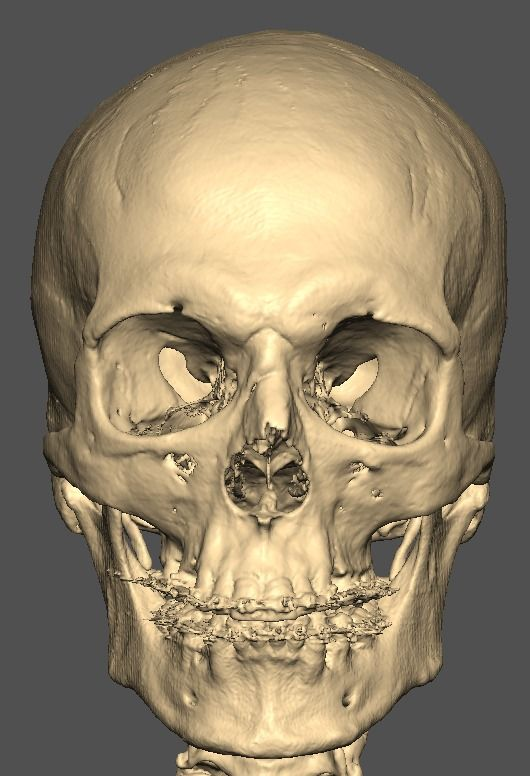

I know a guy who designed this for himself in collaboration with an asian implant company.

Not the final product yet, he is making adjustments as we speak.

Giant and Eppley were the inspiration